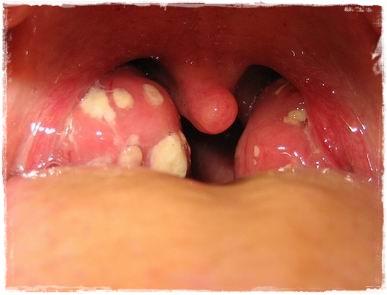

Se trata de un proceso que cursa con fiebre e inflamación del área de la faringe y amigdalas, pudiendo aparecer enrojecimiento, edema, exudado, úlceras, o vesículas.

Las faringoamigdalitis bacterianas tienen un inicio más brusco. Son más frecuentes en invierno y primavera. Asocian fiebre más elevada, inflamación de los ganglios regionales, dolor de garganta intenso y petequias en el paladar y úvula.